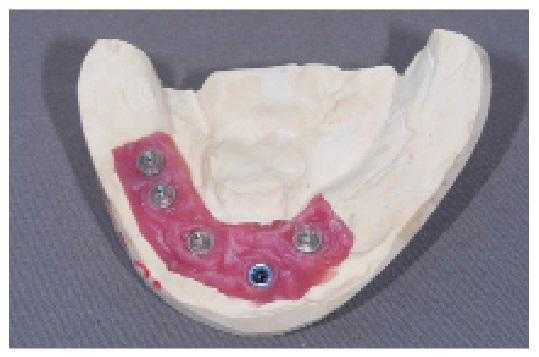

Крепятся зубные протезы такого типа на импланты. Способов крепления 2: кнопочный и балочный.

Балочный способ такой же, как при бюгельном протезировании. Балка выполняет роль патрицы и крепится к имплантам. А матрица находится в теле протеза. За счет балки происходит равномерное распределение жевательной нагрузки.

Кнопочный метод тоже использует патрицу и матрицу, но при этом балка отсутствует. Роль патрицы выполняет абатмент (переходной элемент).

Фото 18. Установка имплантатов на нижней челюсти.